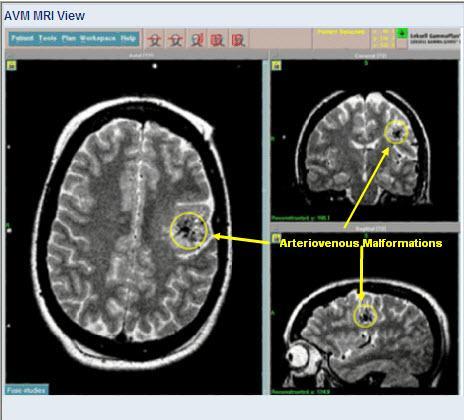

Arteriovenous malformation or AVM is an abnormal connection between veins and arteries, usually congenital This pathology is widely known because of its occurrence in the central nervous system, but can appear in any location.

Symptoms of AVM vary according to the location of the malformation. Roughly 90% of people affected with AVM are asymptomatic; in rare cases its expansion or a micro-bleed from an AVM in the brain can cause epilepsy, deficit or pain.

The most general symptoms of a cerebral AVM include headache and epilepsy, with more specific symptoms occurring that normally depend on the location of the malformation and the individual. Such possible symptoms include: